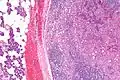

Intermed. mag.

Very high mag.

| Micrograph of an acinic cell carcinoma (right of image) and acinar glands (parotid gland - left of image). H&E stain. | |

Basophilic, bland cells similar to acinar cells. Growth pattern: solid - acinar cells, microcytic - small cystic spaces mucinous or eosinophilic, papillary-cystic - large cystic lined by epithelium, follicular - similar to thyroid tissue.

These tumors, which resemble serous acinar cells, vary in their behavior from locally aggressive to blatantly malignant.